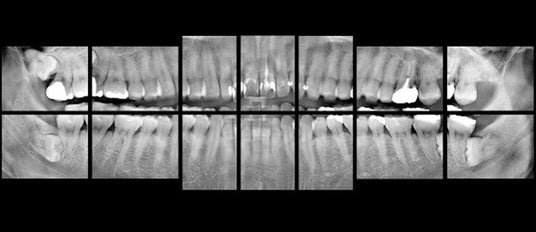

デンタル撮影に関しては、歯が最も明瞭に描出されている断面位置を自動的に作成するオートフォーカス機能を備えており、【図5】に示すように、短時間で全顎のデンタル撮影(10枚法や14枚法)のテンプレートを自動的に作成することができます。

【図5】:歯牙の軌道や傾きに合せた全顎のデンタル画像をオートフォーカス機能で自動的に出力できる機能(図は14枚法テンプレートの例)

歯軸にフォーカスの合った画像